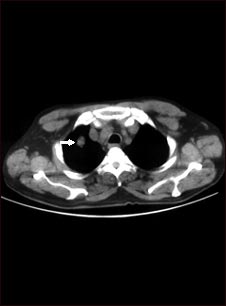

Nódulo pulmonar solitario; TC

TC que muestra una sola lesión (nódulo pulmonar) en el pulmón izquierdo. Se puede ver el nódulo como un círculo claro en la parte superior del área oscura, al lado izquierdo de la imagen. Un pulmón normal aparecería completamente negro en una tomografía computarizada.